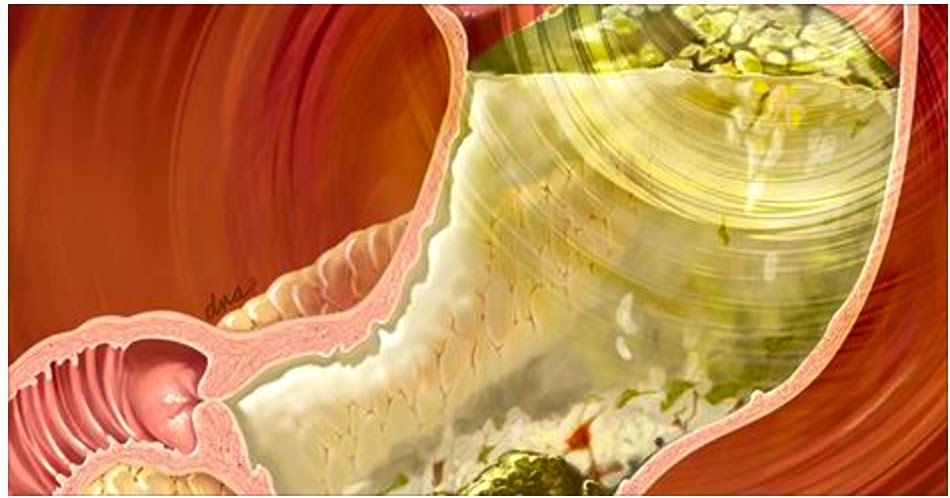

Weight loss surgery arrives in three stages: preparation, surgery and new addition. Each of such stages indicates a major shift within your lifestyle. No surgery is without risk, and which should be taken into consideration, but fat reduction surgery is inside a slightly different category in which requires big changes likewise let last for the rest of the life.

Lap-Band Surgery: This is the identical to gastric bypass. This weight loss surgery method makes regarding a silicone band which can make a reduced pouch involving stomach. Food passes by this smaller pouch instead of in the stomach.